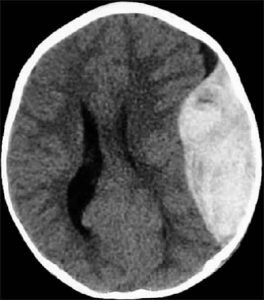

4. If brain CT scan is normal, he will be fine.

No, few times, delayed bleeding in the brain can occur. Small bleeding can be missed by CT or MRI scans.